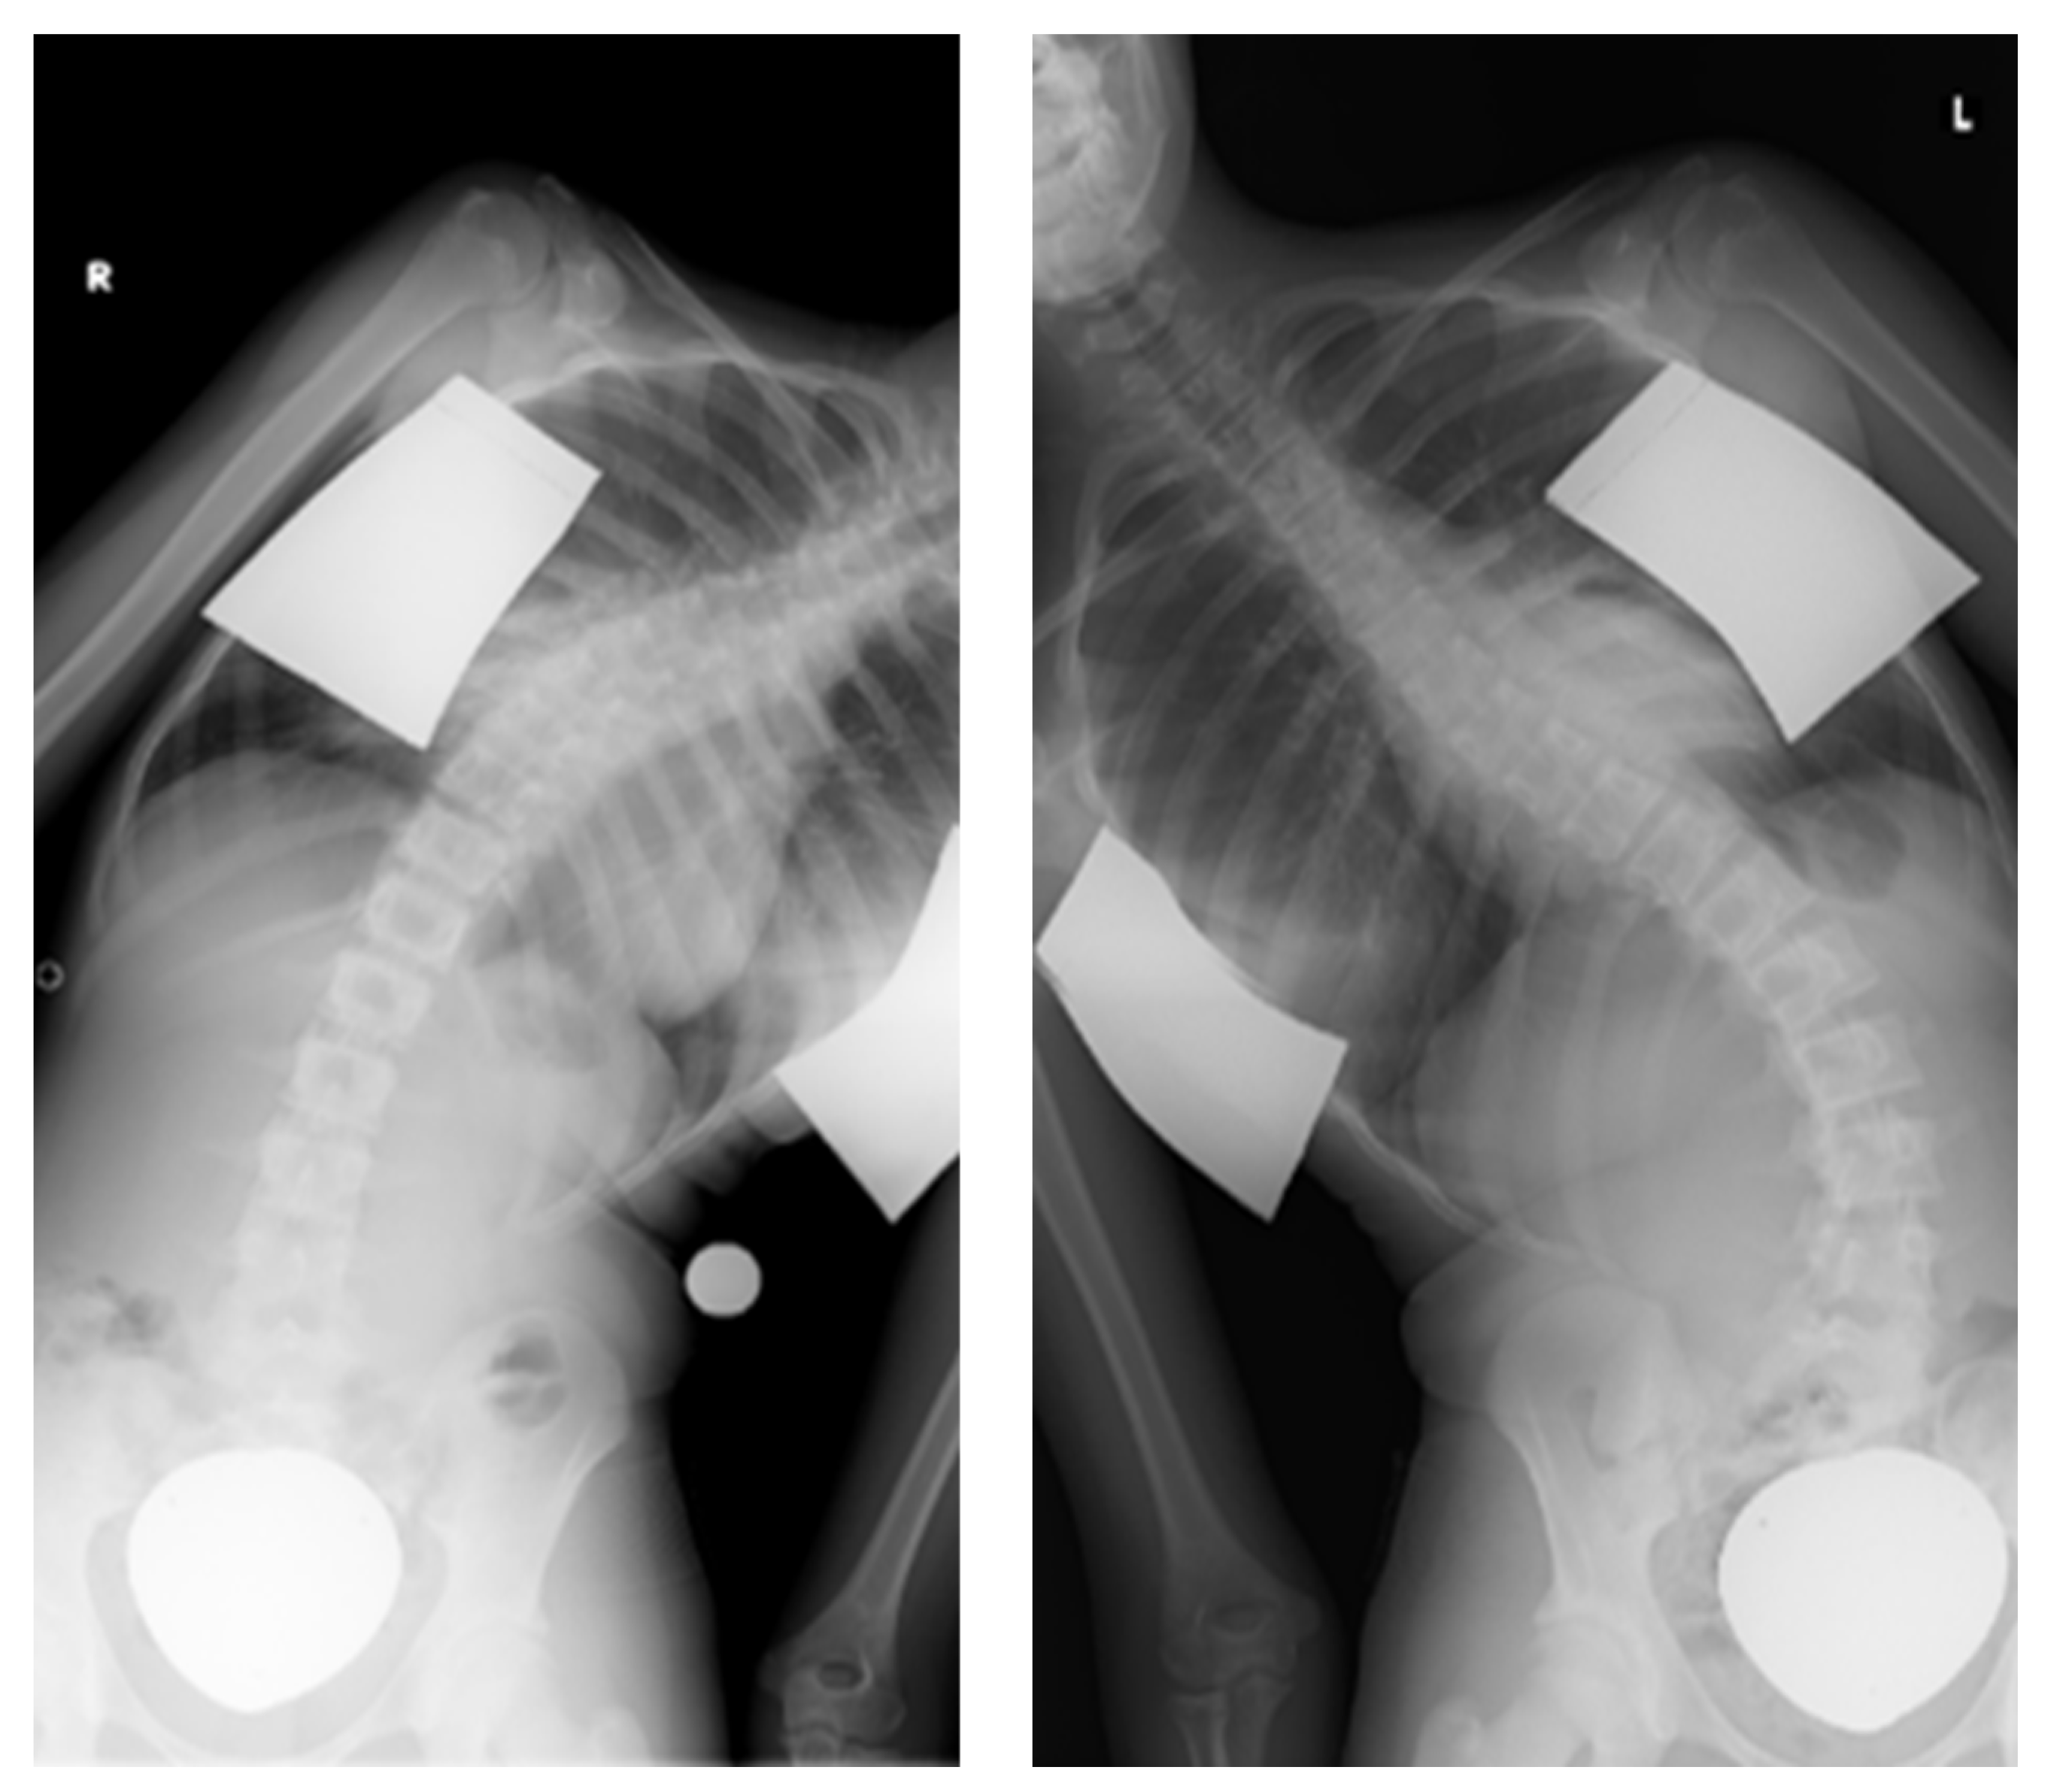

- Trobisch, P.D.; Kobbe, P.; Baroncini, A. Dynamic Scoliosis Correction as Alternative Treatment for Patients with Adolescent Idiopathic Scoliosis: A Non-Fusion Surgical Technique. Z. Orthop. Unfall. 2020, 158, 641–646. [Google Scholar] [CrossRef]

- Floman, Y.; Burnei, G.; Gavriliu, S.; Anekstein, Y.; Straticiuc, S.; Tunyogi-Csapo, M.; Mirovsky, Y.; Zarzycki, D.; Potaczek, T.; Arnin, U. Surgical management of moderate adolescent idiopathic scoliosis with ApiFix®: A short peri- apical fixation followed by post-operative curve reduction with exercises. Scoliosis 2015, 10, 4. [Google Scholar] [CrossRef] [PubMed]

- Floman, Y.; El-Hawary, R.; Lonner, B.S.; Betz, R.R.; Arnin, U. Vertebral growth modulation by posterior dynamic deformity correction device in skeletally immature patients with moderate adolescent idiopathic scoliosis. Spine Deform. 2021, 9, 149–153. [Google Scholar] [CrossRef] [PubMed]